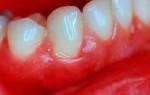

Пародонтоз был известен людям с давних времен, и медики описывали это заболевание еще до нашей эры. Сегодня зубные врачи обладают достаточными знаниями для своевременной диагностики, прогнозирования развития и эффективного лечения пародонтоза. Что такое пародонтоз и как он выглядит (см. фото)? Это заболевание пародонта, которое сопровождается дегенеративными изменениями тканей десны и дистрофией альвеолярных отростков.

Для отличия пародонтоза от пародонтита существует несколько признаков. Во-первых, пародонтоз является редким заболеванием, в то время как пародонтит распространен. Во-вторых, причиной пародонтоза является нарушение клеточного питания, в то время как пародонтит связан с плохой микрофлорой ротовой полости и наличием зубных отложений. В-третьих, пародонтоз затрагивает альвеолярные отростки всей полости рта, тогда как пародонтит может быть локализованным или распространяться на несколько десен. В-четвертых, при пародонтозе отсутствует воспаление десен, а главным процессом является атрофия, в то время как при пародонтите преобладает воспаление. В-пятых, пародонтоз не сопровождается абсцессами, гнойными выделениями, кровотечениями и патологическими зубодесневыми карманами, в отличие от пародонтита. И, наконец, при пародонтозе зубы начинают расшатываться постепенно, с течением времени, в то время как при пародонтите расшатывание зубов происходит уже на ранних стадиях заболевания.